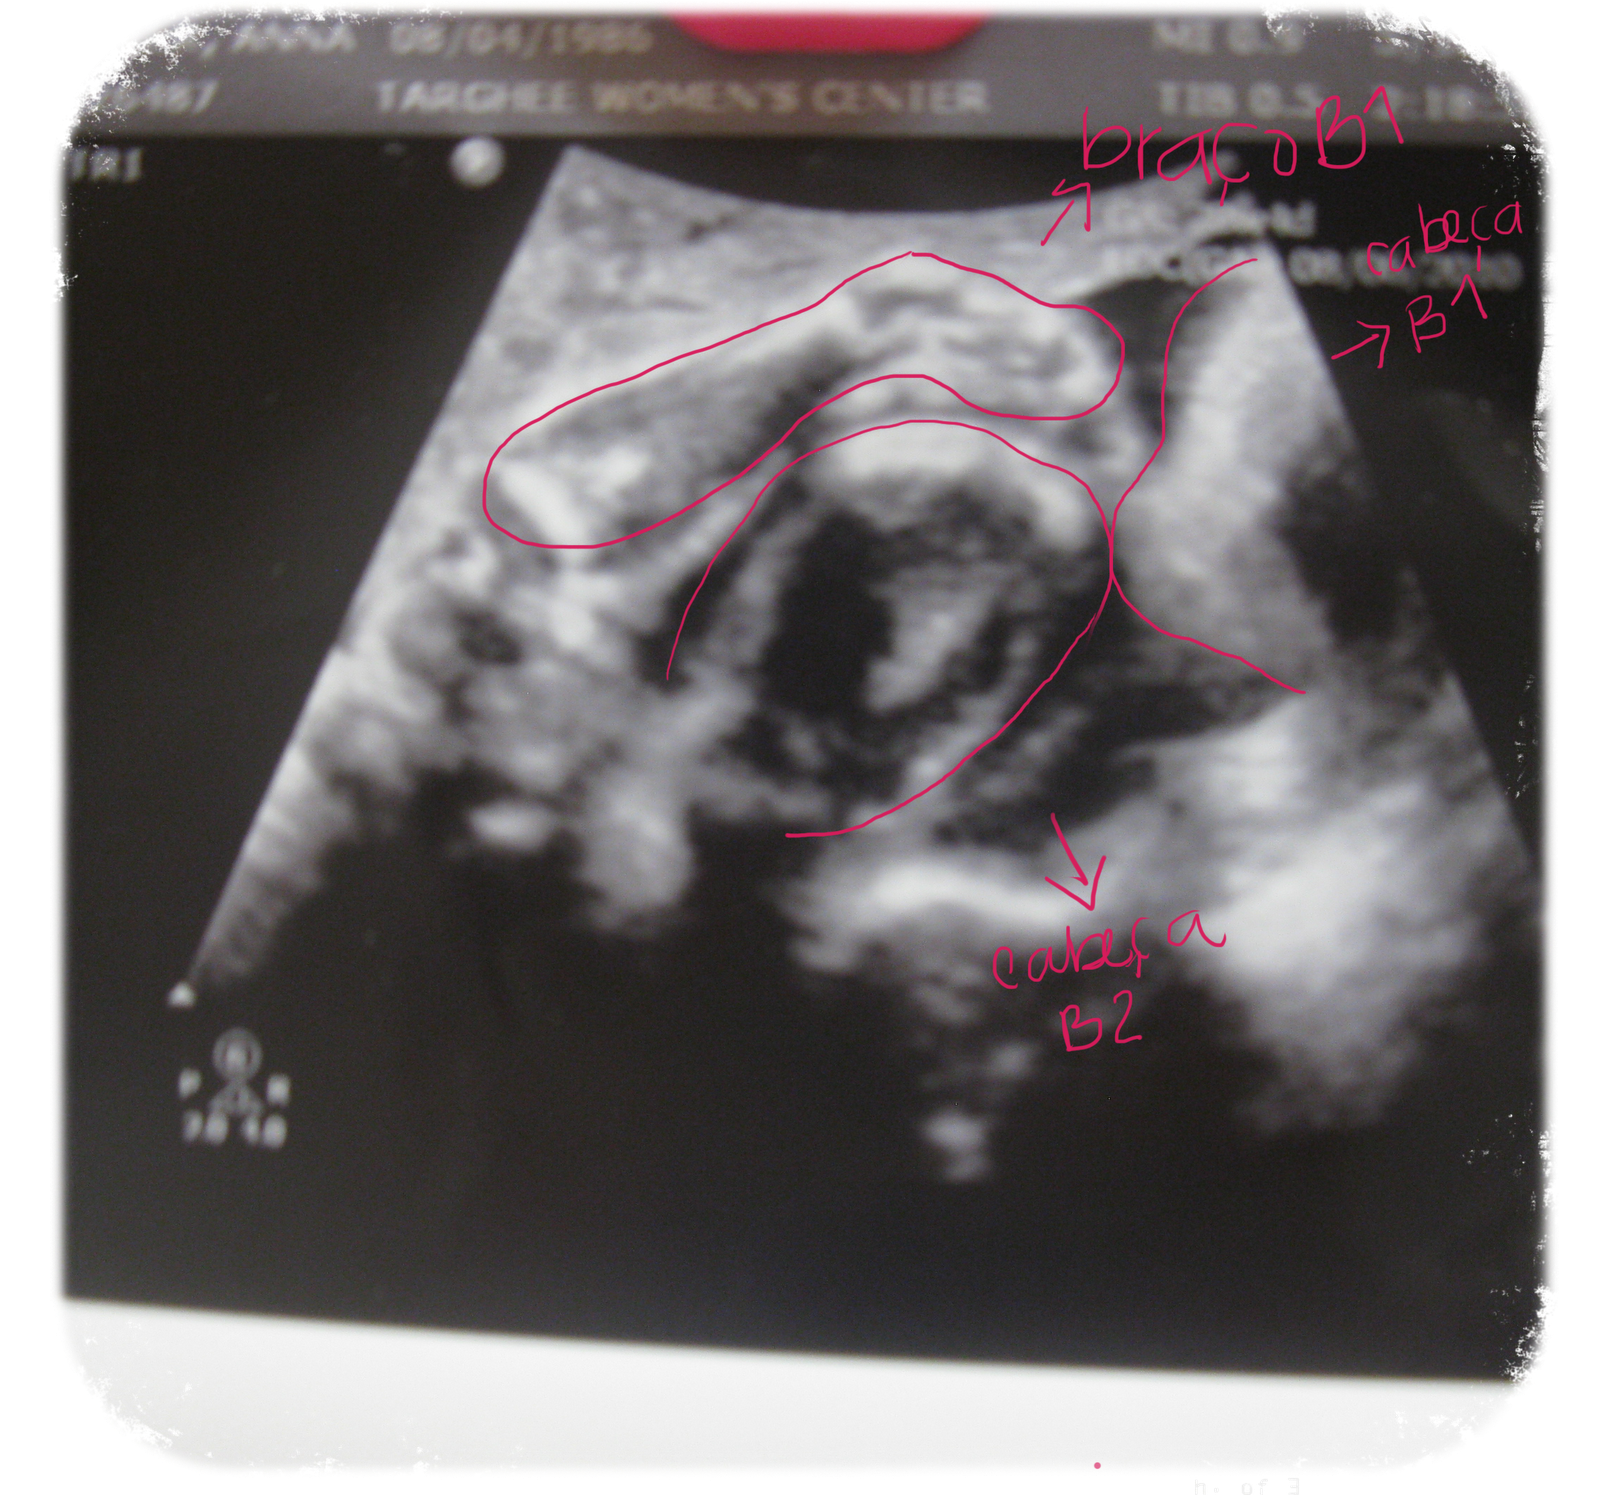

Essa foto foi do ultrasom de hoje - é meio dificil de ver, mas Carol (bebe A) esta com os bracinhos apoiados na cabeça da Gabi (bebe B).

Pra facilitar mais um pouquinho...

Não são lindas?! Já com tanto cabelinho e até lacinho!!!! :oP